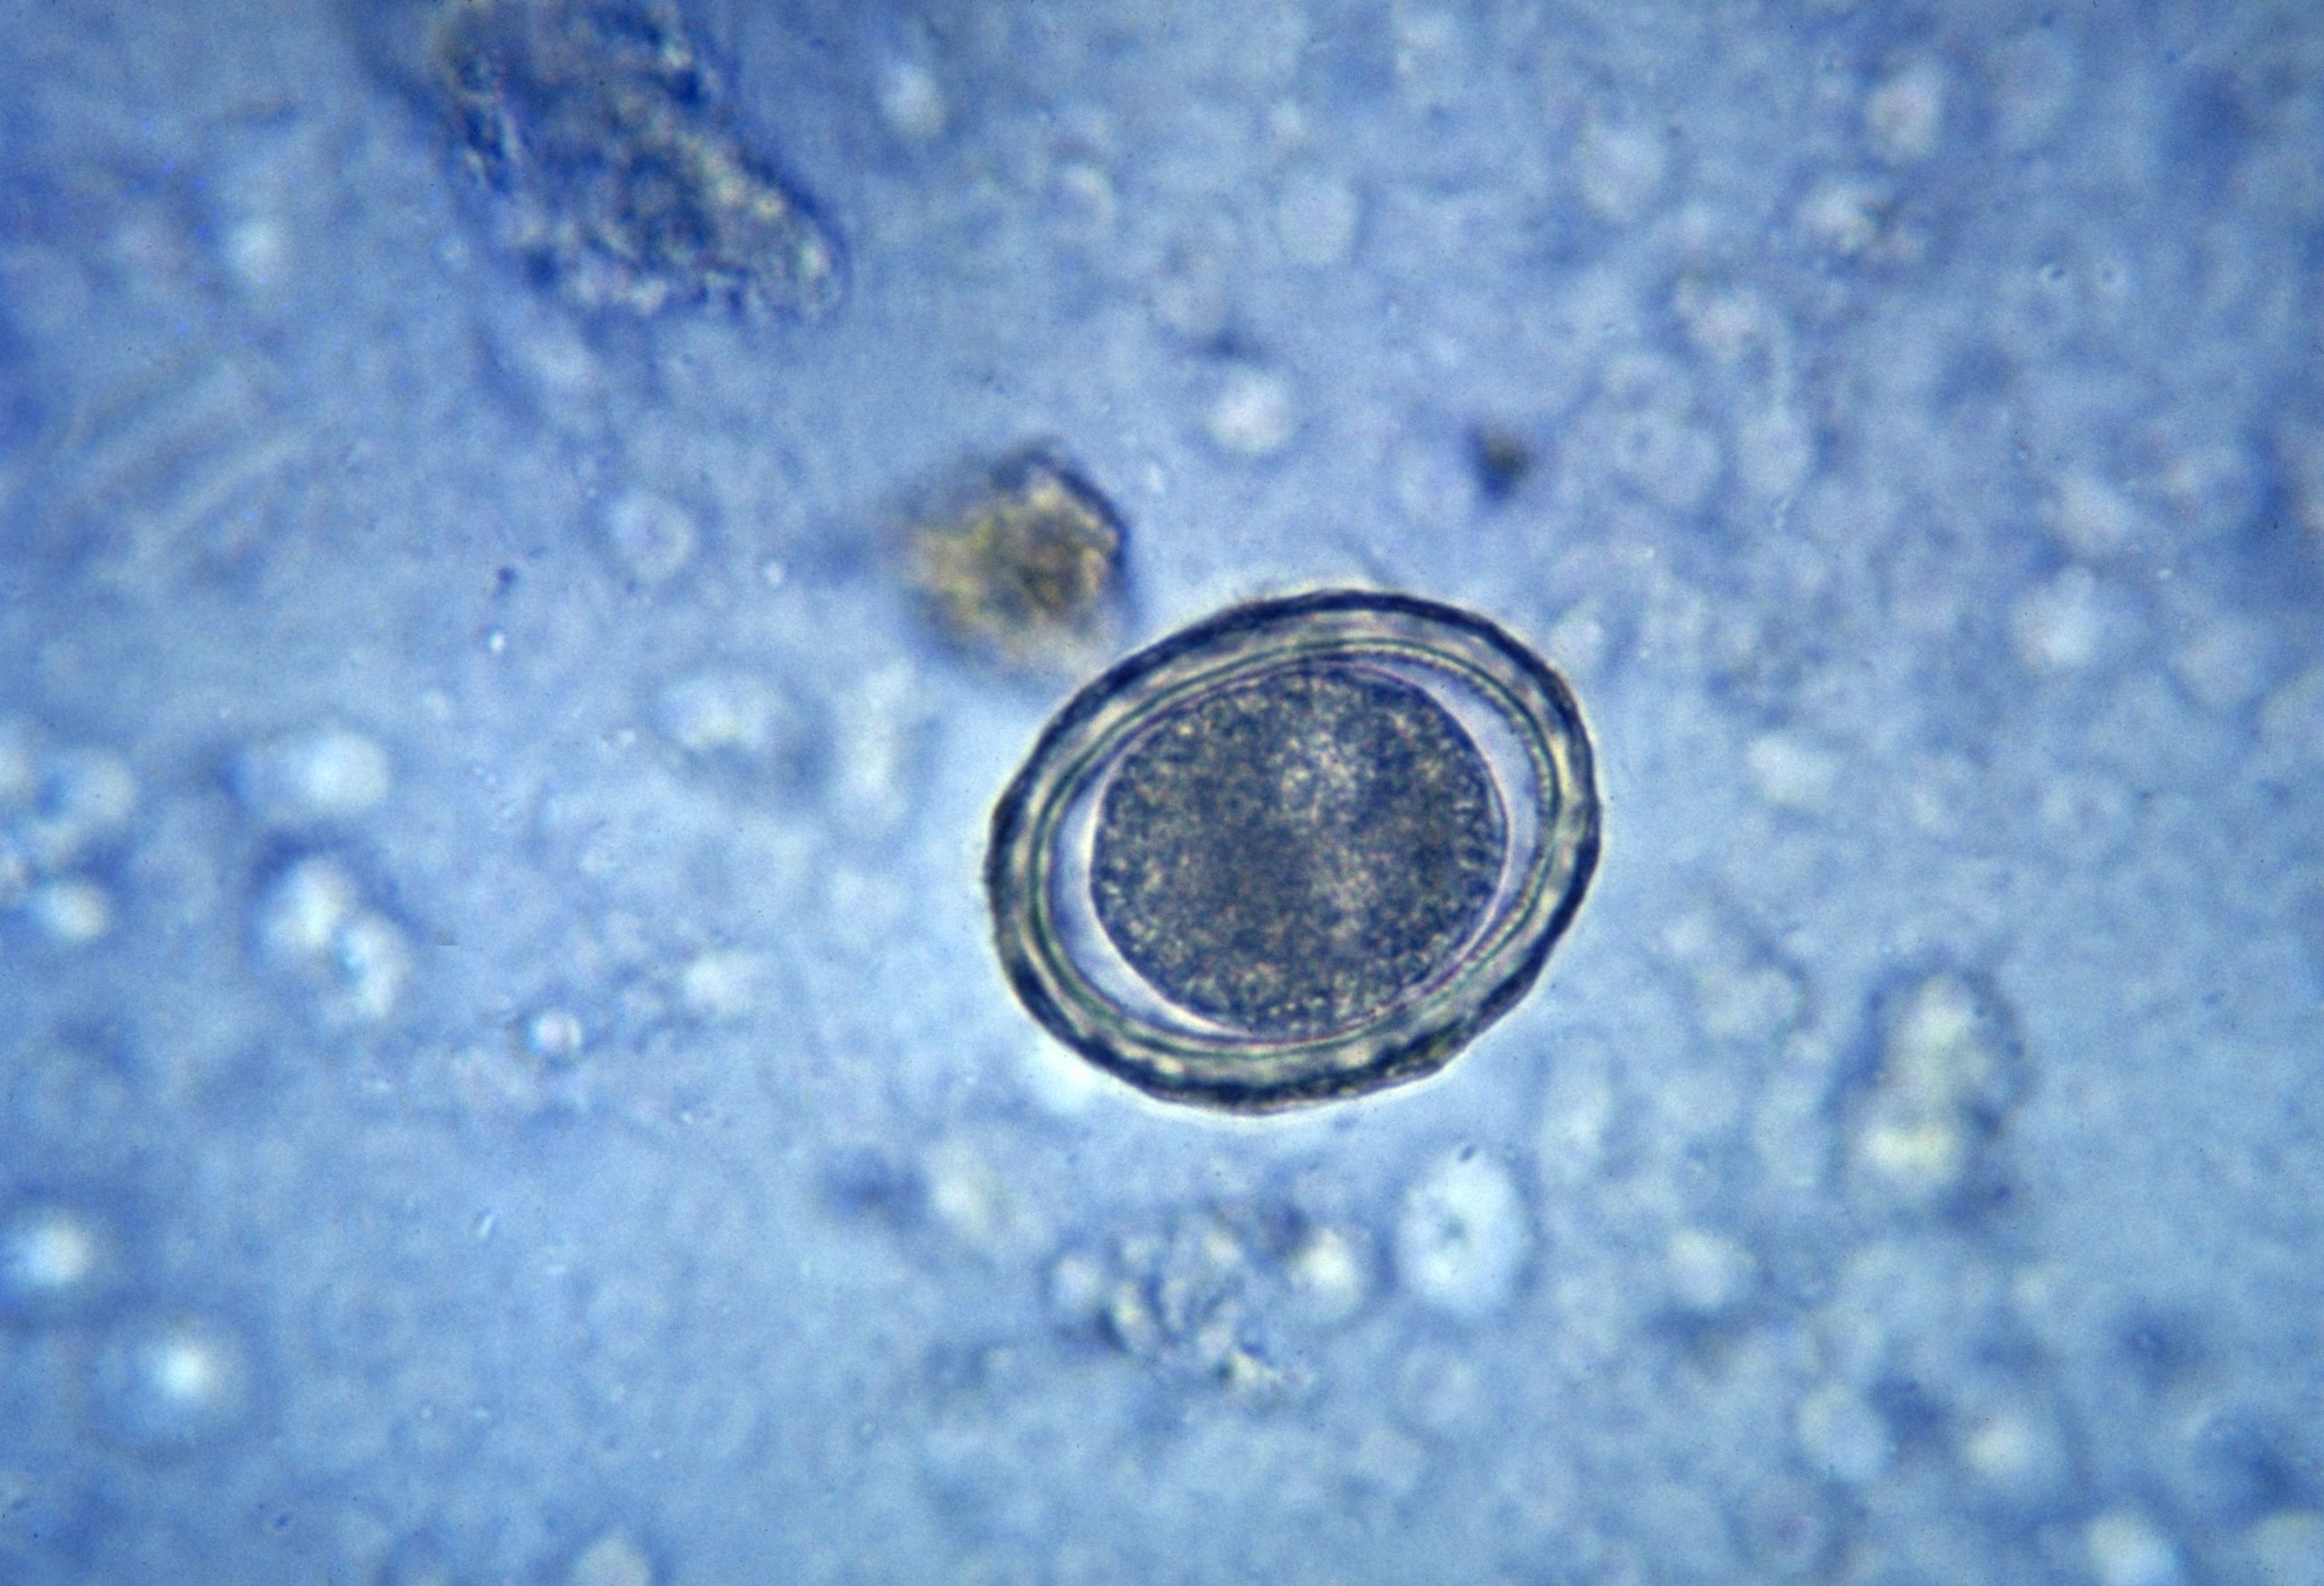

È stato riconosciuto come un focolaio di infezione da vermi intestinali, noti col nome scientifico di ascaris lumbricoides, quello diffusosi fra i giovani studenti dell’istituto comprensivo Parini Rovigliano di Torre Annunziata, nel Napoletano. Il parassita, che ad oggi è stato riscontrato in oltre venti tra bambini e ragazzi che frequentano la struttura, potrebbe tuttavia aver già trovato il modo di raggiungere altre persone e, forse, altri istituti della zona.

Lungo tra i quindici ed i quaranta centimetri nella sua fase adulta, l’ascaris lumbricoides può raggiungere il corpo umano tramite l’assunzione di acqua o alimenti contaminati dalle feci di un soggetto infetto.  Le uova, così giunte nell’intestino del corpo ospite, si schiudono rapidamente dando la possibilità alle larve di spostarsi tra i vari organi attraverso il flusso sanguigno. Tra i sintomi più comuni della patologia, che va curata con una terapia farmacologica lunga circa tre settimane, si riscontrano febbre, perdita di appetito, ostruzione intestinale e respiro affannoso. Il personale medico dell’Asl 3 Napoli sud, che ha avviato le procedure di contenimento e profilassi all’interno dell’istituto oplontino, raccomanda a tutti, per evitare il contagio, di lavare accuratamente le mani e il cibo che si intende consumare.